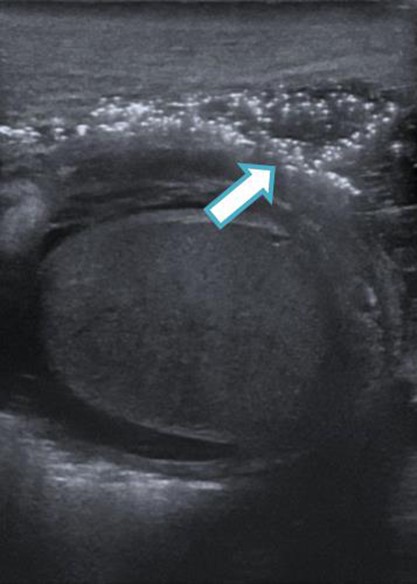

An urgent scrotal ultrasound demonstrated evidence of gas within the deep tissues of the scrotum but no abscess as shown in Fig. 1. Subsequently an abdomino-pelvic CT scan revealed multi-loculated collections in the right iliac fossa, suggesting perforated appendicitis with secondary extension of gas down the spermatic cord into the scrotum, as shown in Figs 2 and 3.